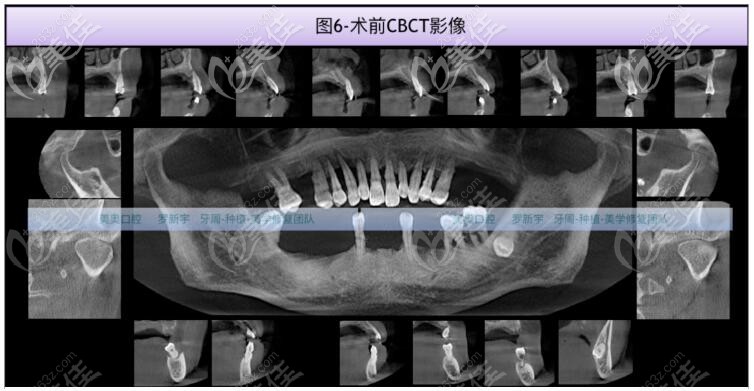

在羅醫(yī)生的面診,結合CT拍片檢查,大爺?shù)娜毖绤^(qū)骨質(zhì)II-III類,骨量充足,但15、14、13、12、11、21、22、23、24、25、37、36、48中到重度骨吸收。17、33、43輕中度骨吸收。

術前1周檢查血常規(guī)、凝血功能及傳染5項,全口牙周基礎治療后,大爺在美奧口腔做了NOBEL諾貝爾全口即刻種植牙。